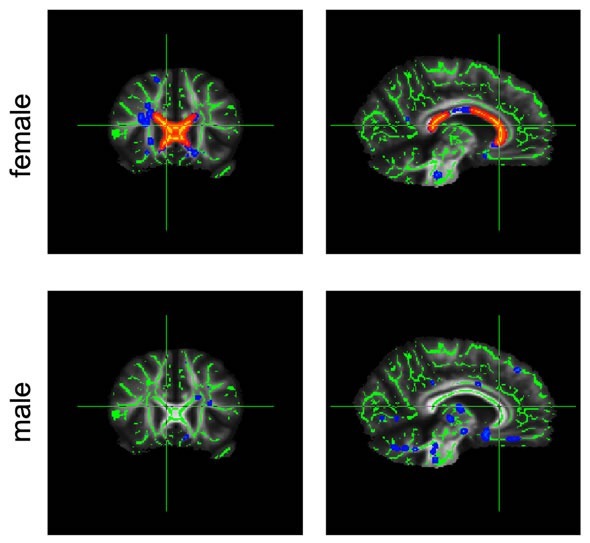

corpus callosumChanges in diffusion in the corpus callosum (marked red) are much greater in obese female participants than in their male counterparts.

The differences in diffusion, which are likewise observed in premature aging of the brain tissue, were more dominant in female participants and covered a greater area of the corpus callosum. This is the first study to show systematic sex-related differences in the relationship between weight and the brain. This could possibly be because connections between the brain hemispheres generally show differences between men and women.